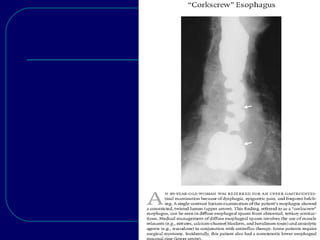

 Ba swallow: prominent, spontaneous, nonpropulsive, tertiary

contractions give rise to a “corkscrew” esophagus,but this not

pathognomonic as it also observed in asymptomatic elderly;

presbyesophagus.

DIFFUSE ESOPHAGEAL SPASM: Uncommon motor disorder presents clinically with chest pain, dysphagia, or both.  It remains one of the most commonly sought (but uncommonly found) in patients with non-cardiac chest pain.  Symptoms /signs are intermittent, so diagnosis may be difficult.  Like achalasia, associated with degeneration of the nerves in Auerbach’s plexus& in rarely evolve to achalasia.  Ba swallow: prominent, spontaneous, nonpropulsive, tertiary contractions give rise to a “corkscrew” esophagus,but this not pathognomonic as it also observed in asymptomatic elderly; presbyesophagus.